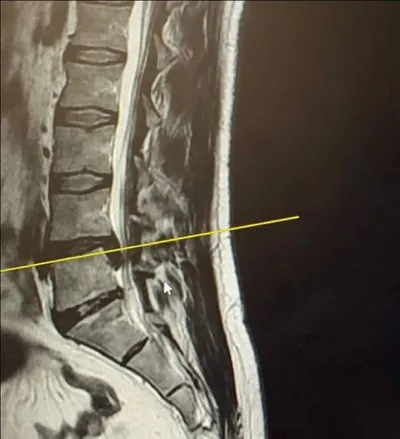

Почти опоздал за инвалидностью... Или нет. 🏥🤯🧐😥🧠👨‍🦽 В неврологический кабинет поликлиники №666 его привезла жена на машине, но в кабинет он вошёл сам, слегка прихрамывая. Андрей, 45 лет, стро

3 мар. 2026 г.

638 15 2